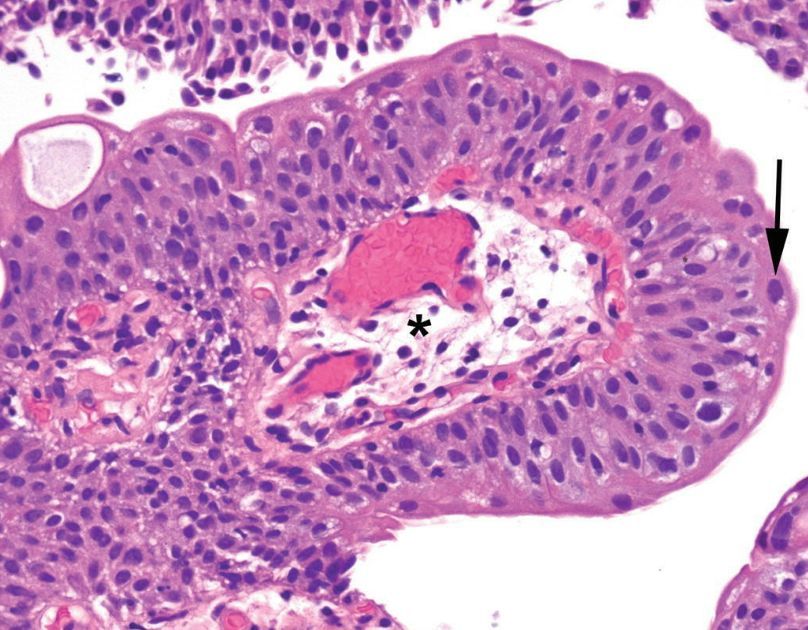

Schistosomiasis

Note the visible eggs, which appear as dark purple ovals with single spines. Appears in a background of granulomatous cystitis.

Eggs may be calcified (as seen on the front) or not (as seen below). When uncalcified, they look almost like a large clump of giant cells.